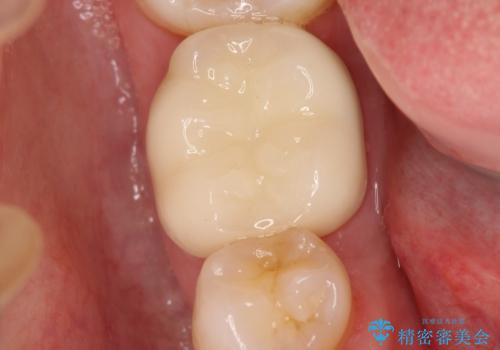

やはり内部では少量の虫歯がありましたので、拡大鏡使用して虫歯を除去しました。

今回精度の高い治療を行うことで、再治療の可能性を限りになく小さくできました。